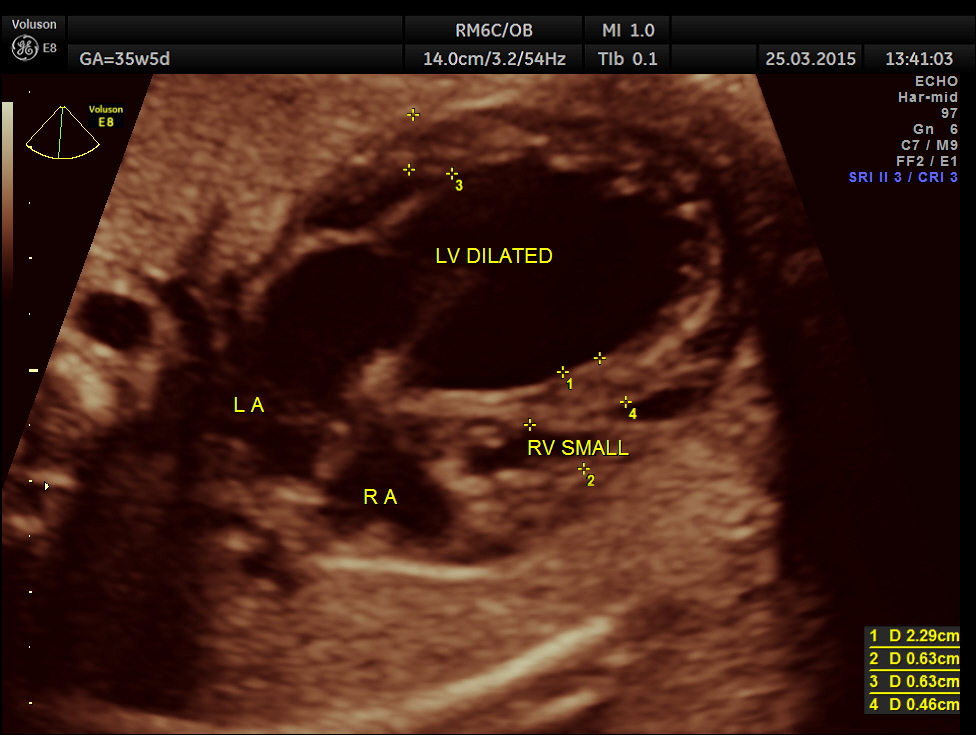

Cardiomegaly with dilated left ventricle and small right ventricle were obvious.

This is a 3 D image showing similar findings. Both pictures also show the pulmonary veins draining into left atrium and the left atrium opening into left ventricle and the right atrium opening into right ventricle. ( free wall attachment of the mitral valve leaflet,moderator band seen in the right ventricle and the tricuspid shows a septal leaflet.)

The 4 chamber view showed LV to be dilated.